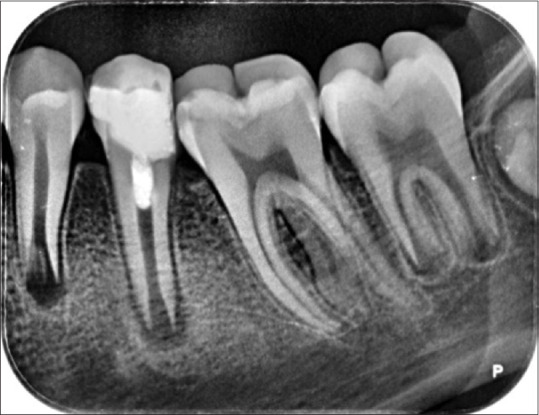

再生牙髓治疗是治疗牙尖开放坏死的一种权宜之计。再生牙髓治疗领域的临床研究取得了可喜的成果。本病例系列的主要目的是介绍再生牙髓治疗的影像学和临床表现。

Regenerative endodontics is an expedient therapeutic strategy for necrotic teeth with open apex. The promising result of clinical research in the regenerative endodontic treatment field is published. The main goal of this case series is to present the radiographic and clinical findings of the regenerative endodontic procedure.